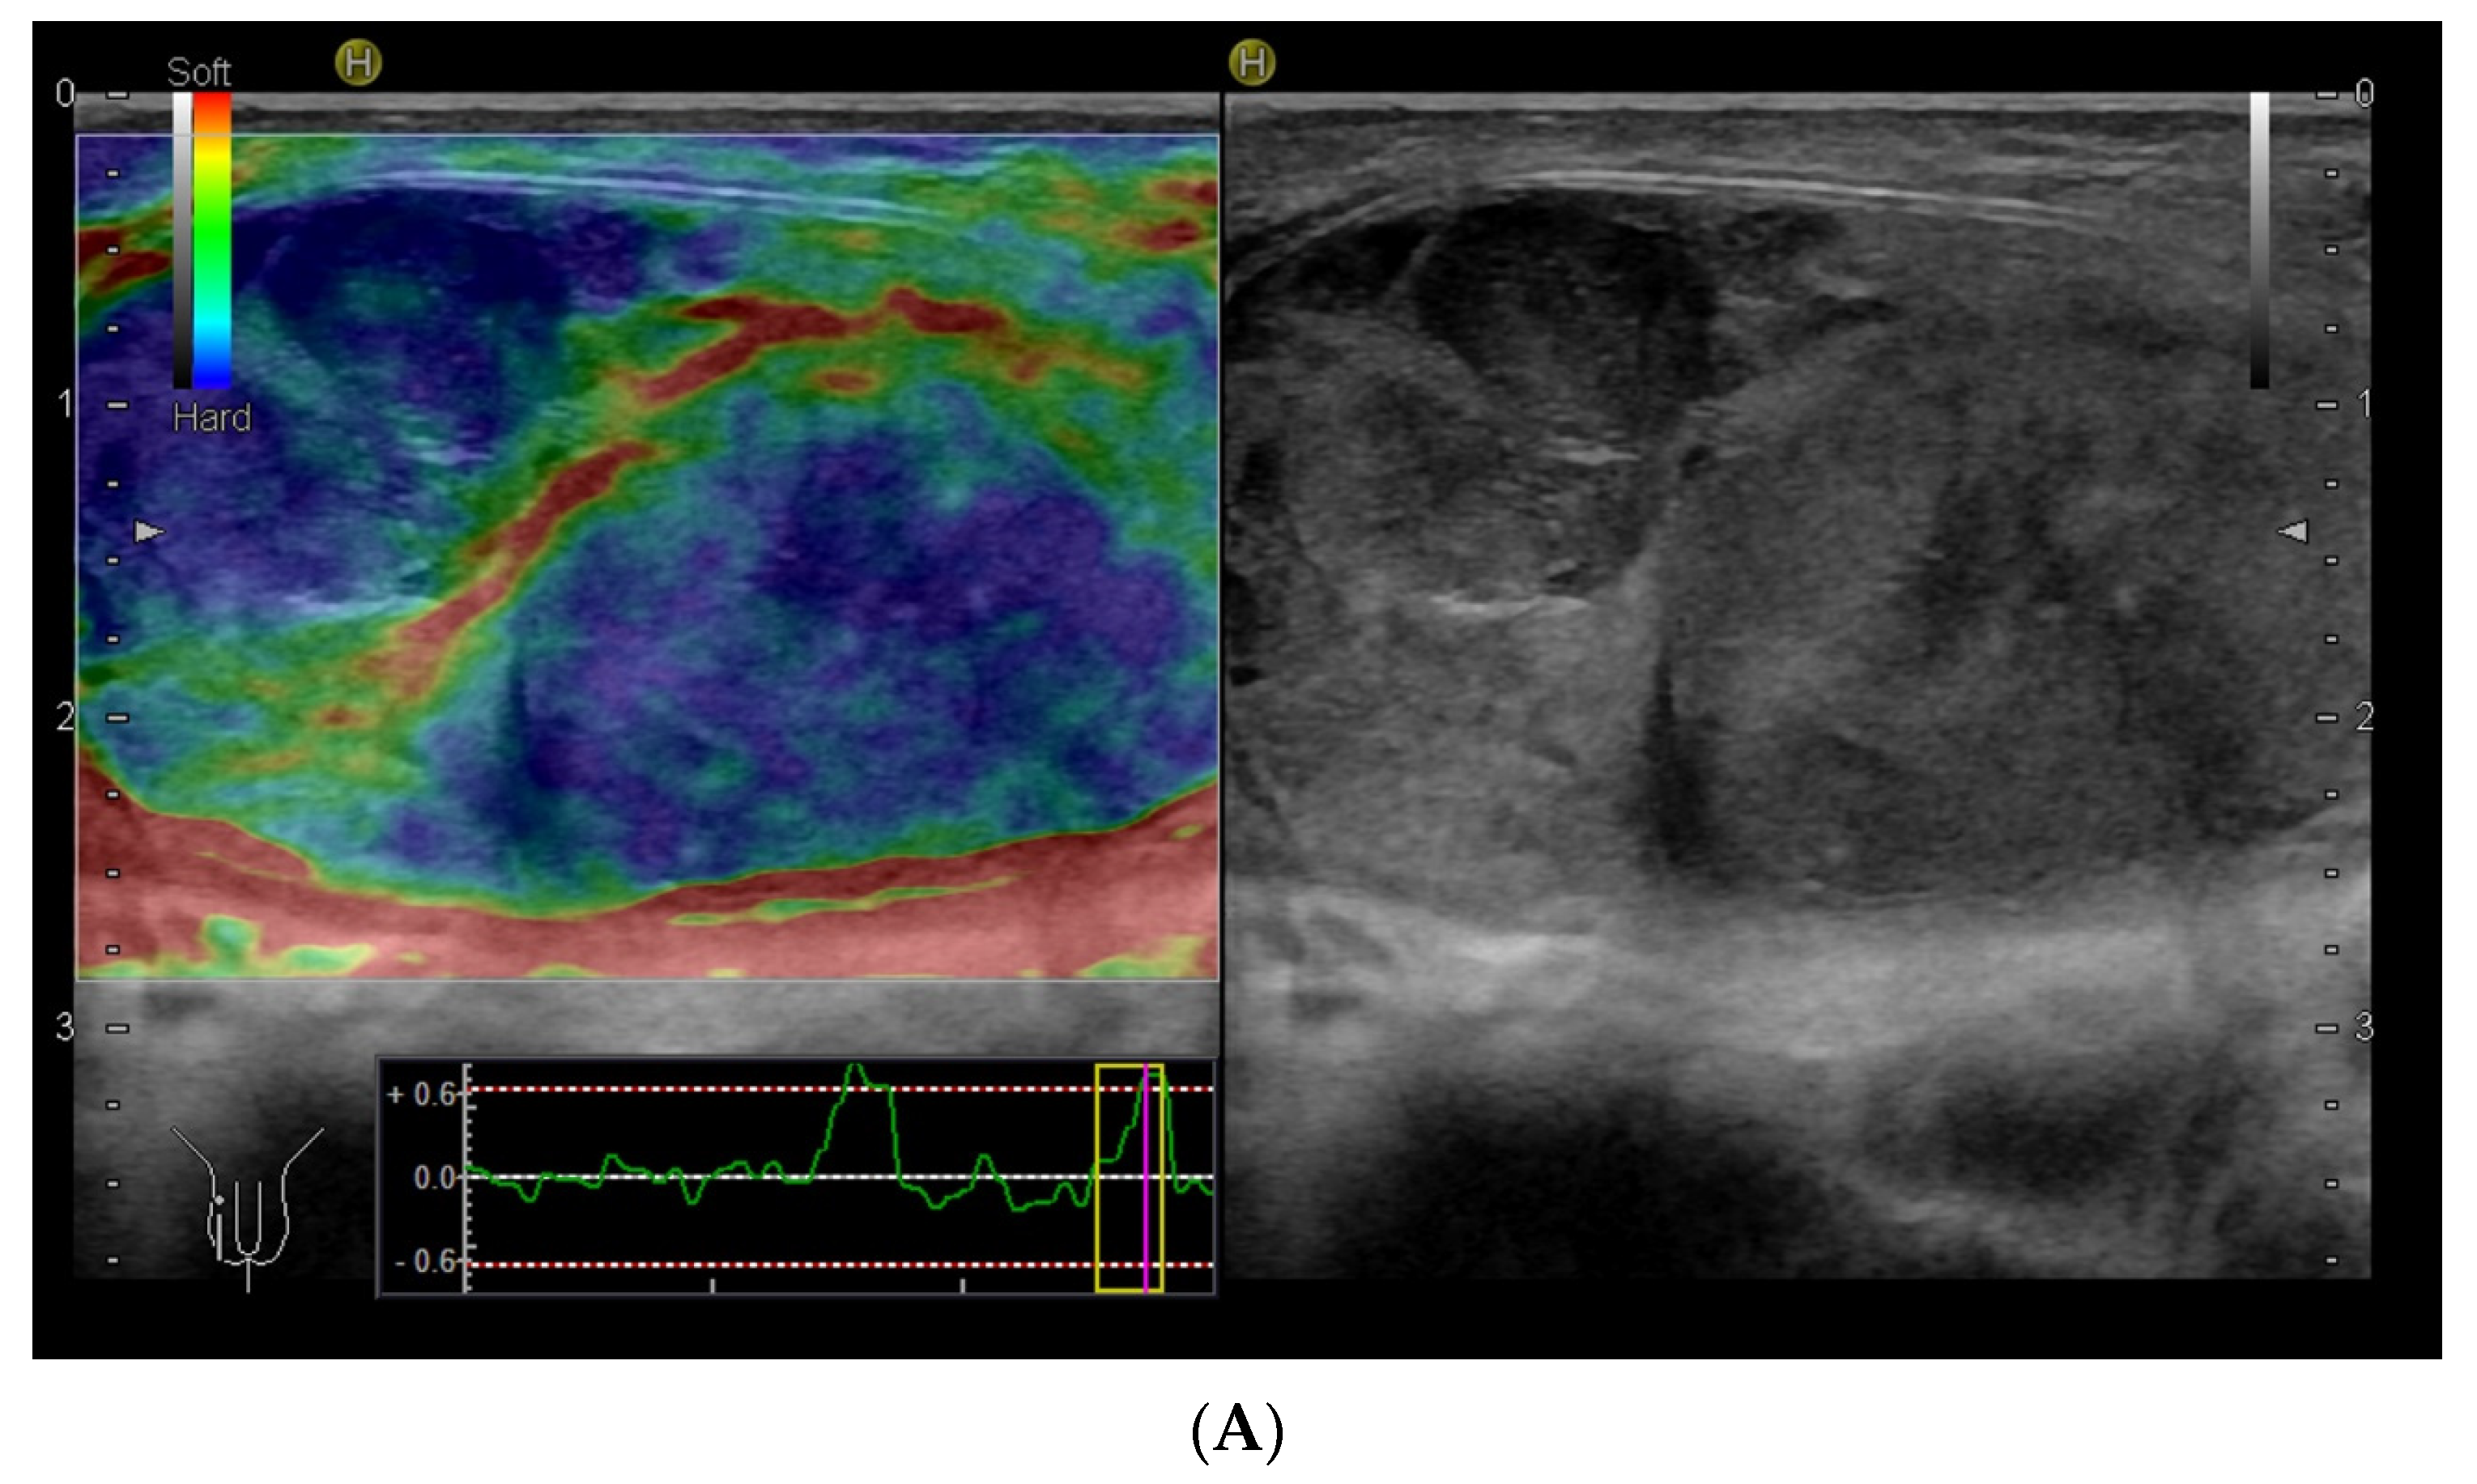

4.3. Elastography in Testicular Lesions